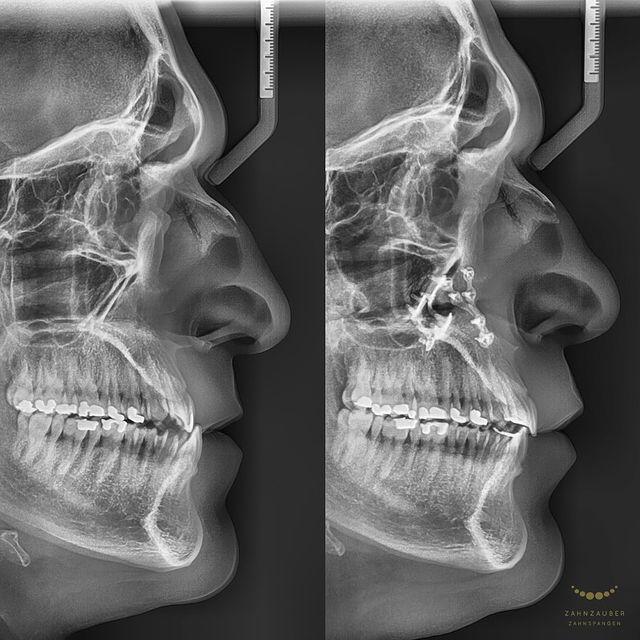

Vorher: Der Patient kam mit einer asymmetrischen Klasse-II-Malokklusion, einem Engstand und einem Vorbiss von 14 mm. Zusätzlich lag eine retrognathe Mandibula vor, was die Kieferstellung beeinträchtigte und funktionelle Probleme verursachte.

Nachher: Nach der zweijährigen Behandlung, in der vier Zähne entfernt und der Unterkiefer operativ korrigiert wurden, wurde ein dauerhafter Retainer eingesetzt, um die ideale Position der Zähne langfristig zu stabilisieren. Der Patient verließ die Praxis mit einem harmonisch ausgerichteten und funktional verbesserten Gebiss.